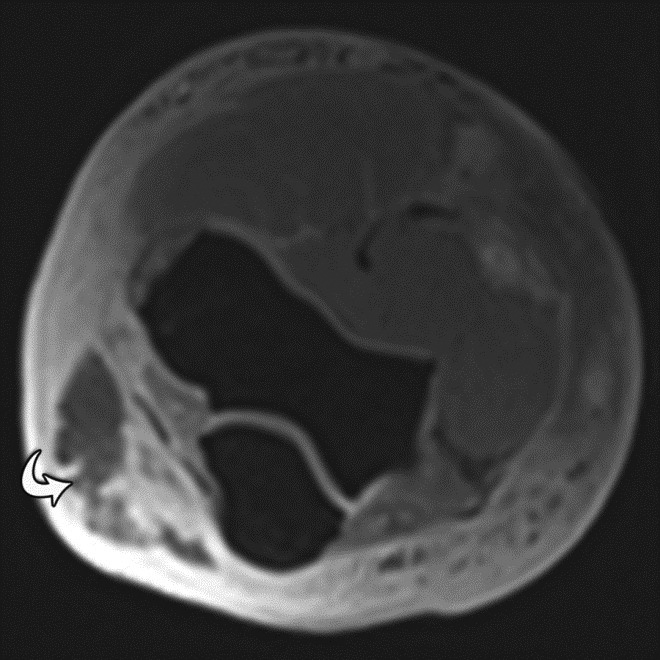

Pulsation Artifact. Axial T2-weighted fat-saturated MR image of the pelvis demonstrates femoral artery pulsation resulting in ghost images (arrowheads) obscuring the anterior labra and simulating femoral head lesions bilaterally.